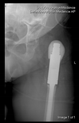

The radiological examination allowed us to verify the close bone-to-implant contact and the unchanged position of the implant during follow-up.

In all the cases operated with the above-described targeting procedure, the stems of the cups remained between the cortical bone surfaces without perforation of the linea terminalis, as shown by postoperative radiographs. There were no complicated surgical situations. In 16 cases, the wound healings were uneventful, and the hips were able to bear weight again after postoperative rehabilitation.